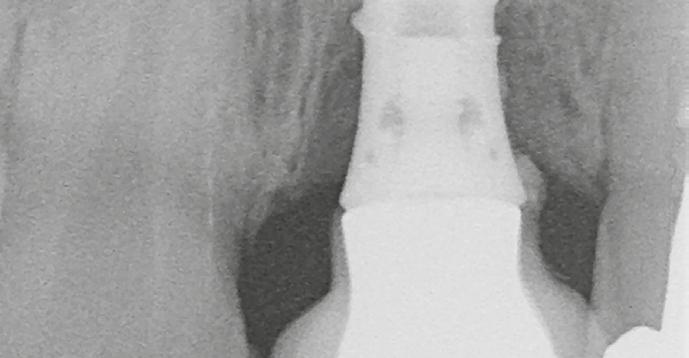

Mind a hat implantátum esetén kétlépcsős műtétet végeztünk. Minden sebészeti eljárást bódítás, illetve preoperatív szisztémás antibiotikus terápia nélkül végeztünk. A négy eset közül kettőnél leukocitában és vérlemezkében gazdag fibrint (L-PRF) alkalmaztunk a beavatkozás során (IntraSpin, BioHorizons; 2. táblázat). Minden esetben a pontos CERALOG menetvágási (maximum 15 ford./perc) és fúrási (maximális fúrási fordulatszám: 550–800 ford./perc) protokollt követtük. Az összes implantátumot manuálisan helyeztük be 35 Ncm maximális nyomatékkal. Az implantátumokba PEEK zárócsavar került (2. ábra). A lágyszövetet atraumatikus, felszívódó varrattal, szorosan zártuk/összevarrtuk. A műtétek után szövődmények nem jelentkeztek. A pácienseket arra kértük, hogy a műtét utáni héten naponta kétszer öblögessenek klórhexidinnel (PERIO-AID, 0,05%, DENTAID). Az alsó állcsontnál három hónapos, a felső állcsontnál öt hónapos gyógyulási időt vettünk figyelembe. Három hónap (1. eset) és öt hónap (2., 3. és 4. eset) elteltével a műtétek második stádiumát helyi érzéstelenítés mellett végeztük. A gyógyu-

lási csavarokat (PEEK titáncsavarral) maximum 15 Ncm-rel húztuk meg (3–6. ábra). Az összes implantátum kiváló stabilitást mutatott (a mérésekhez Periotestet használtunk, a Medizintechnik Gulden jóvoltából), és teljesen osszeointegrálódott. Ezt a radiológiai vizsgálatok is megerősítették.

2. a–d ábra: PEEK zárócsavarok az implantátumokba helyezve, 1. eset (a). 2. eset (b). 3. eset (c), 4. eset (d). 3. a–b ábra: Röntgenfelvételek három hónap után (a) és a gyógyulási csavarok behelyezve (b, 1. eset). 4. a–b ábra: Röntgenfelvételek öt hónappal később (a) és a gyógyulási csavarok behelyezve (b, 2. eset). 2. táblázat: Az implantátum tulajdonságai.

tottuk (az okklúziós koncepciók alapján az implantációs pótlások nem voltak vezető fogak, és csak könnyű érintkezéseket alakítottunk ki, amelyeket artikulációs papírral ellenőriztünk). A páciensek instrukciókat kaptak a megfelelő szájhigiénére vonatkozóan, összpontosítva a fogköz kefékkel történő tisztítására. Végső kontroll röntgenfelvétel készült. A PEEK felépítmény nem radioopák, így az implantátum és a korona közötti távolság könnyen meghatározható a röntgenfelvételen: a felépítmény megfelelően illeszkedik az implantátumban, ha az implantátum válla és a korona alsó széle közötti rés 0,55 mm a röntgenfelvételen (8–11. ábra)